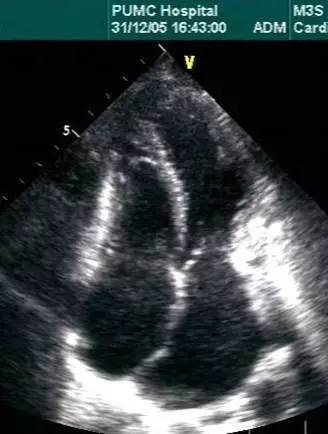

l超声心动图是一线检查

l经胸超声心动图

超声心动图

对心包厚度识别不是优势

cardiac tamponade and pulsus paradoxus